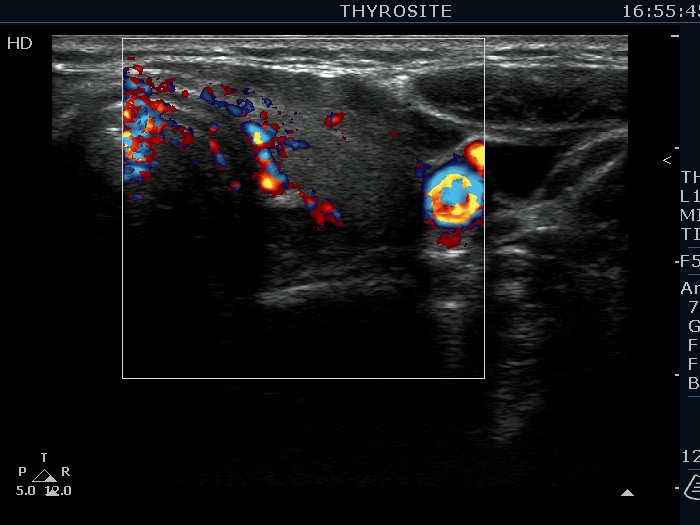

Left lobe, transverse view, color Doppler mode. The vascularization is not specific.